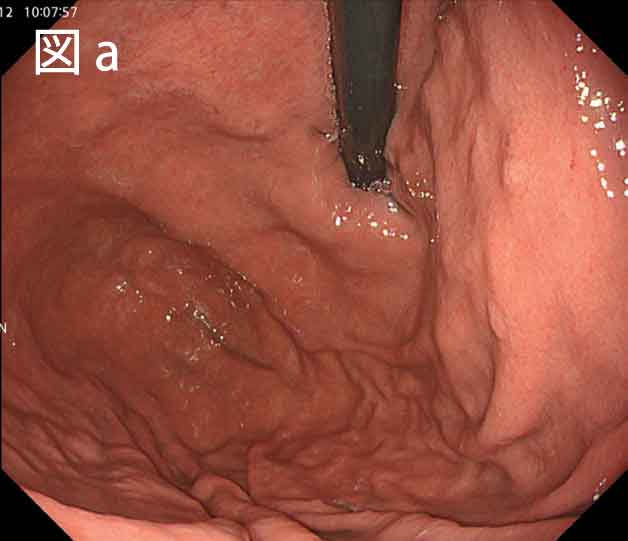

さらに、EVIS X1に搭載されたTXI では、通常光の情報に基づき、「明るさ補正」、「構造協調」、「色調強調」の3つの要素を最適化する画像強調処理が行われます。特にTXI モード 1では3つの要素を処理することにより粘膜表面の微細な構造、色調変化をとらえることが容易になります。このため胃炎の観察においては微細な表面凹凸変化、炎症による発赤、萎縮性変化による退色調変化が画像強調されることにより炎症・萎縮境界が明瞭になります(図d)。